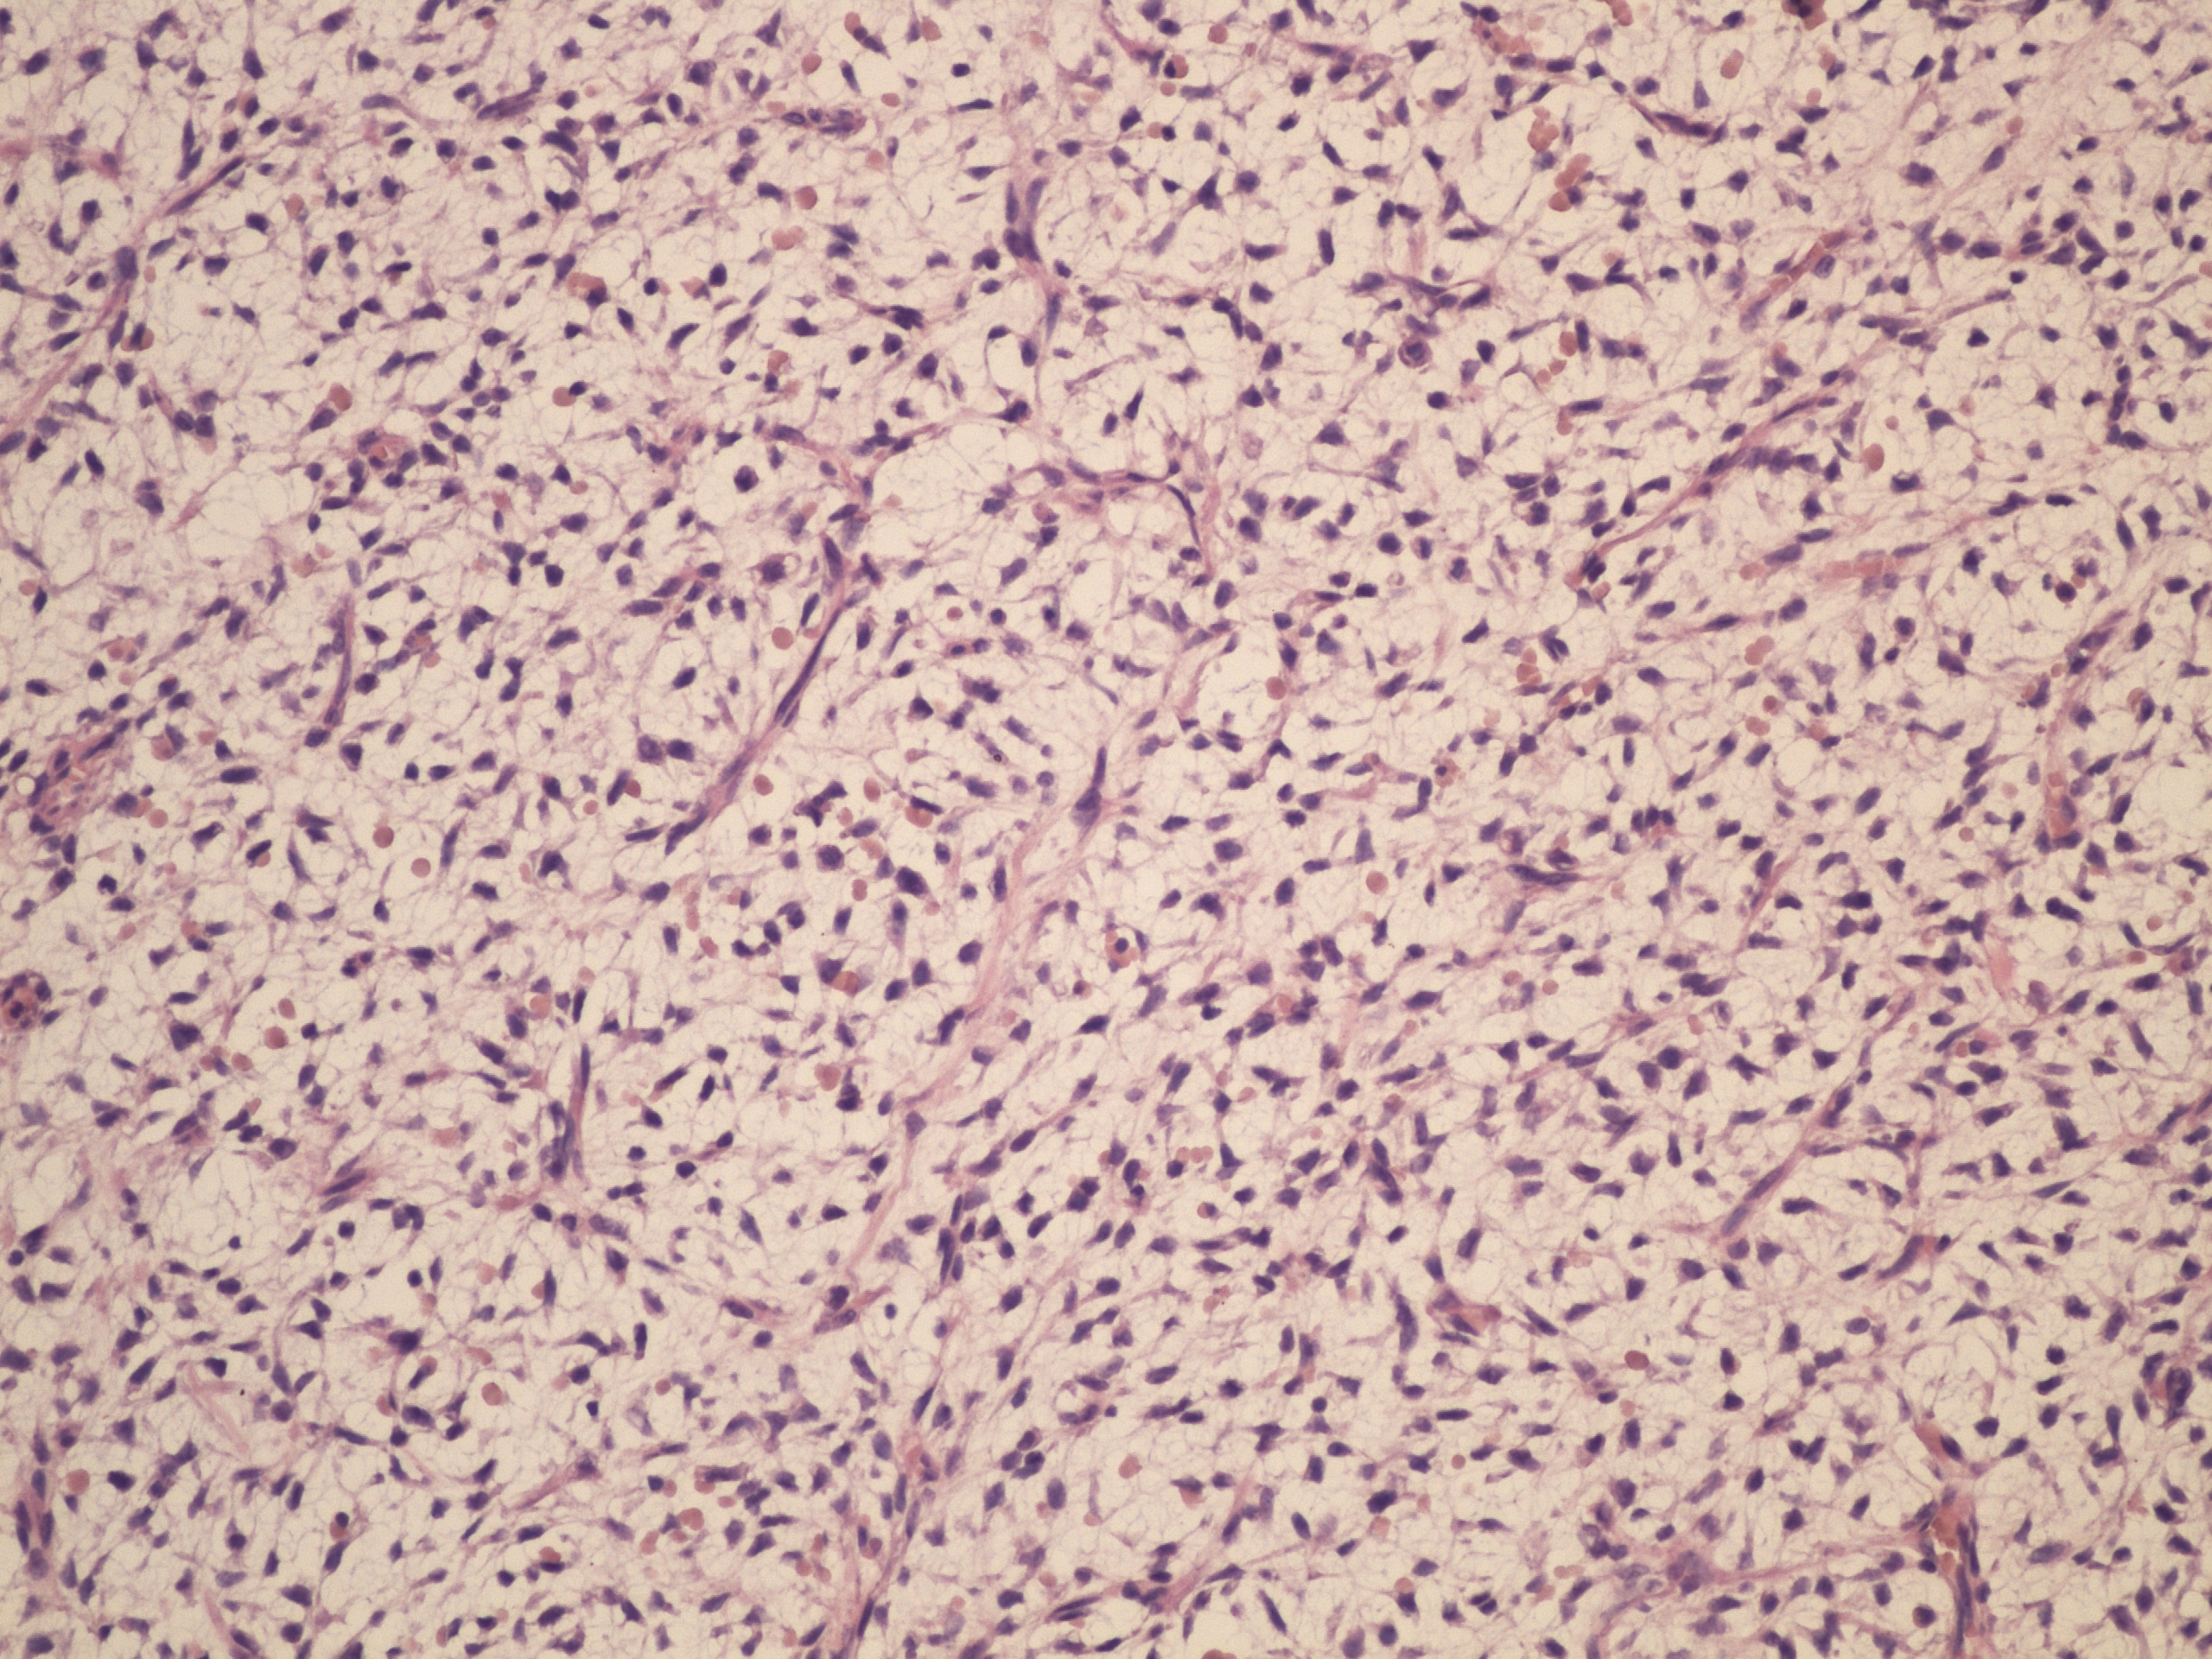

Preparát č.3 a č.4 - nádor z granulárních buněk

Struktury

- nádorová tkáň

- pseudoepiteliomatózní hyperplazie dlaždicového epitelu sliznice jícnu

- granulární cytoplazma nádorových buněk